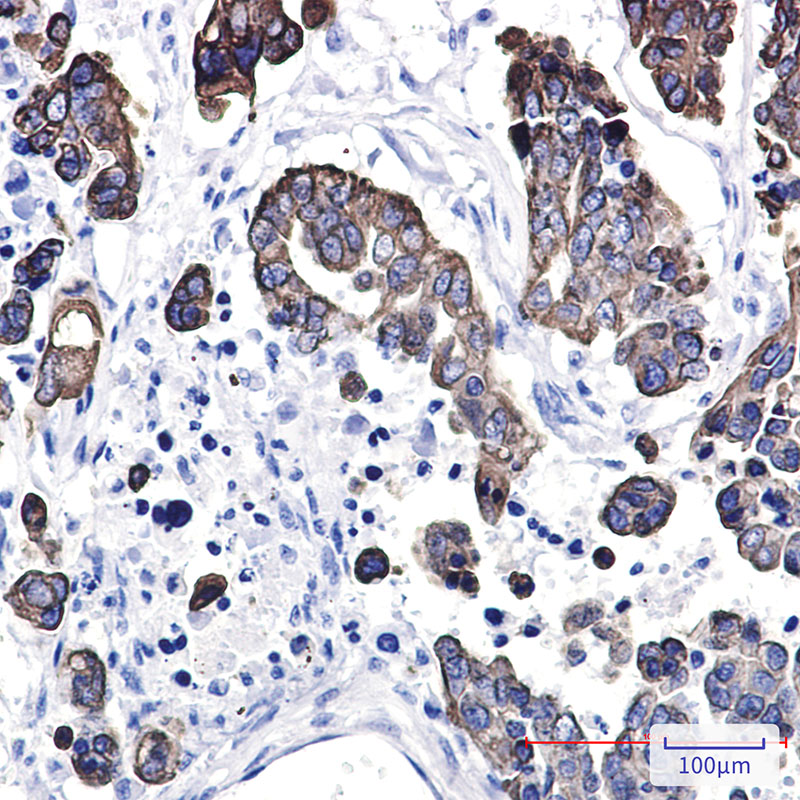

Immunohistochemistry analysis of paraffin-embedded Human Cholangiocarcinoma using Cytokeratin 8 antibody. High-pressure and temperature Sodium Citrate pH 6.0 was used for antigen retrieval.